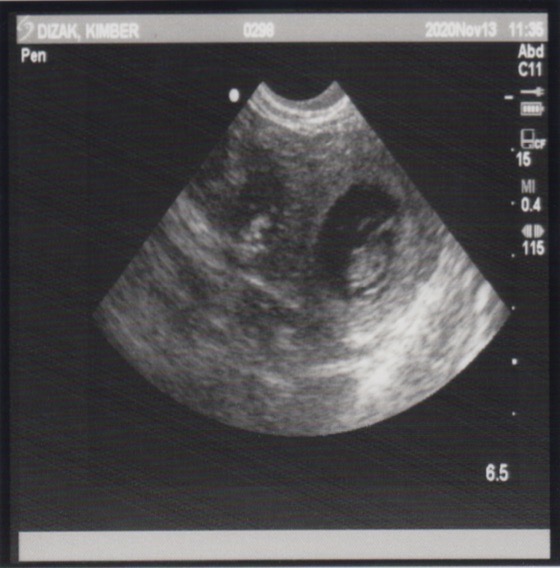

November 13, 2020 – Ultrasound

Since this was an artificial insemination and the success rate a bit lower than natural breedings, we wanted to have an ultrasound done to see if there are any little beings growing inside of Miss Kimber. Well, our repro vet confirmed this morning that Kimber is indeed pregnant!